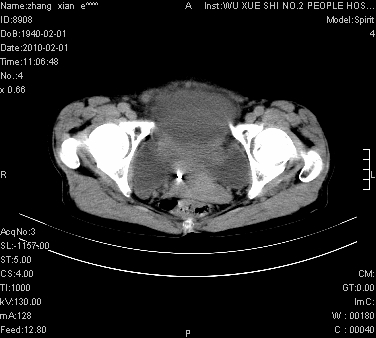

标题: CT24434:70岁 女 腹胀,腹水原因待查 [打印本页]

标题: CT24434:70岁 女 腹胀,腹水原因待查

大量腹水,脾脏囊性占位,子宫颈占位,右侧腹股沟淋巴结肿大,建议+c,先查妇科。

腹盆腔大量积液,子宫增大,子宫颈增大外形不规则,内见低密度影,膀胱后壁显示不清,右腹股沟肿大淋巴结,脾脏囊性占位,子宫颈占位,子宫颈癌?建议增强。

子宫、宫颈占位?转移性腹水?肝性腹水?脾脏囊性占位,囊肿?血管瘤?淋巴瘤?